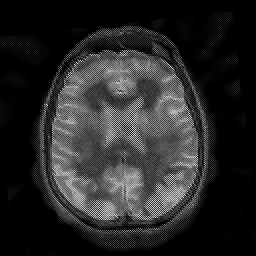

Alzheimer's disease: overlay -- Slice #33

[Home][Help][Clinical] Slice 33